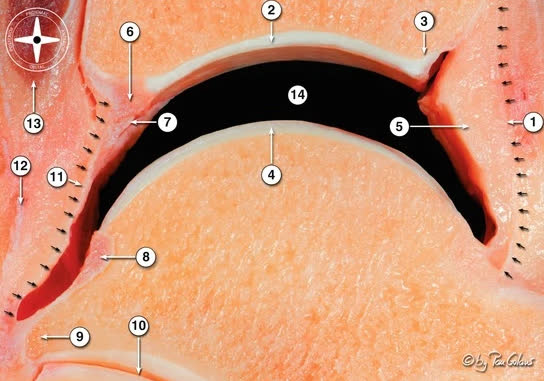

Костная анатомия дистального отдела большеберцовой кости

Суставная поверхность дистального отдела большеберцовой кости (плафон) имеет вогнутую форму в сагиттальной плоскости, что обеспечивает конгруэнтность с блоком таранной кости. Площадь суставной поверхности плафона составляет примерно 10 см². Передний край плафона (margo anterior, передний бугорок Chaput/Tillaux-Chaput) выступает дистальнее заднего, формируя переднюю «губу», ограничивающую тыльное сгибание. Задний край (задняя лодыжка, фрагмент Volkmann) образует заднюю опору суставной поверхности и место прикрепления задней порции межберцового синдесмоза.

Медиальная лодыжка является продолжением медиальной колонны и местом прикрепления дельтовидной связки. Вырезка малоберцовой кости (incisura fibularis) расположена на латеральной поверхности дистального отдела большеберцовой кости и формирует ложе для дистального межберцового синдесмоза.

Метафиз большеберцовой кости имеет тонкий кортикальный слой и губчатую структуру, что определяет характерный паттерн разрушения при осевой нагрузке: вдавливание блока таранной кости в плафон с формированием импакции центральной зоны и расщеплением периферических фрагментов.

Колонная классификация Topliss (2005)

В оригинальной работе (JBJS Br, 2005) описаны 10 типов переломов, объединённых в 2 семейства, с выделением 6 типичных фрагментов. Упрощённая дидактическая интерпретация разделяет дистальный отдел большеберцовой кости на 3 колонны:

- Переднелатеральная колонна (фрагмент Chaput/Tillaux-Chaput)

- Медиальная колонна

- Заднелатеральная колонна (задняя лодыжка, Volkmann)

Каждая колонна представляет собой независимую суставно-метафизарную единицу, требующую индивидуальной фиксации. Межнаблюдательская надёжность: умеренная [Qiu et al., 2020]. 3D КТ-реконструкция значительно повышает надёжность классификации [Keiler et al., Arch Orthop Trauma Surg, 2020].

Четырёхколонная теория (Chen, 2019)

Расширение классификации Topliss с выделением задней колонны как самостоятельной единицы. По данным Lou et al. (2023), задняя колонна повреждается в 88% переломов пилона (125 из 142) — это наиболее часто повреждаемая колонна. Задние варианты пилона (низкоэнергетические) составляют до 63% всех переломов пилона в некоторых сериях.

Практическое значение: при переломах AO/OTA 43-C не всегда необходима фиксация всех колонн — стабилизация 2–3 ключевых колонн может быть достаточной [Bakan et al., Injury, 2023].

Ни одна классификация изолированно не определяет хирургический доступ. Рекомендуется комбинация: AO/OTA для оценки тяжести + колонная классификация для планирования доступов [Bastias & Lagos, Foot Ankle Clin, 2020].

Пятиколонная классификация (Liu, 2025)

Наиболее современная классификация, основанная на 3D-картировании переломов и конечно-элементном анализе распределения нагрузки (244 перелома пилона, 2018–2024). Выделяет 5 колонн:

- Медиальная колонна — перелом медиальной лодыжки

- Передняя колонна — передняя 1/3 суставной поверхности дистального отдела большеберцовой кости (за исключением медиальной лодыжки)

- Средняя (центральная) колонна — задние 2/3 суставной поверхности, исключая медиальную колонну и заднюю лодыжку. Отражает импакцию центральной зоны плафона — ключевой компонент, не выделявшийся в предшествующих классификациях

- Заднелатеральная колонна — задняя лодыжка (фрагмент Volkmann)

- Латеральная колонна — дистальный отдел малоберцовой кости + повреждение дистального межберцового синдесмоза, рассматриваемые как единая функциональная единица

Линия перелома на суставной поверхности имеет характерное V-образное распределение с ветвями, расходящимися от зоны медиальной лодыжки и вырезки малоберцовой кости. Наиболее частый паттерн — трёхколонные переломы, затем двухколонные.

Межнаблюдательская надёжность: каппа = 0,653 (P<0,001); внутринаблюдательская: каппа = 0,708 (P<0,001) — сопоставима с AO/OTA и превосходит ранние колонные классификации [Liu et al., Orthop Surg, 2025; PMID: 39579007].

Пятиколонная теория — это продолжение теории колонн, которая преобразовалась тем, что задняя колонна была переосмыслена на среднюю (или привычнее для нас, центральную) и добавлена постеролатеральная колонна (фрагмент Фолькмана). Клинических и практических данных по данной классификации пока недостаточно, чтобы однозначно делать какие-то выводы о таком подходе.